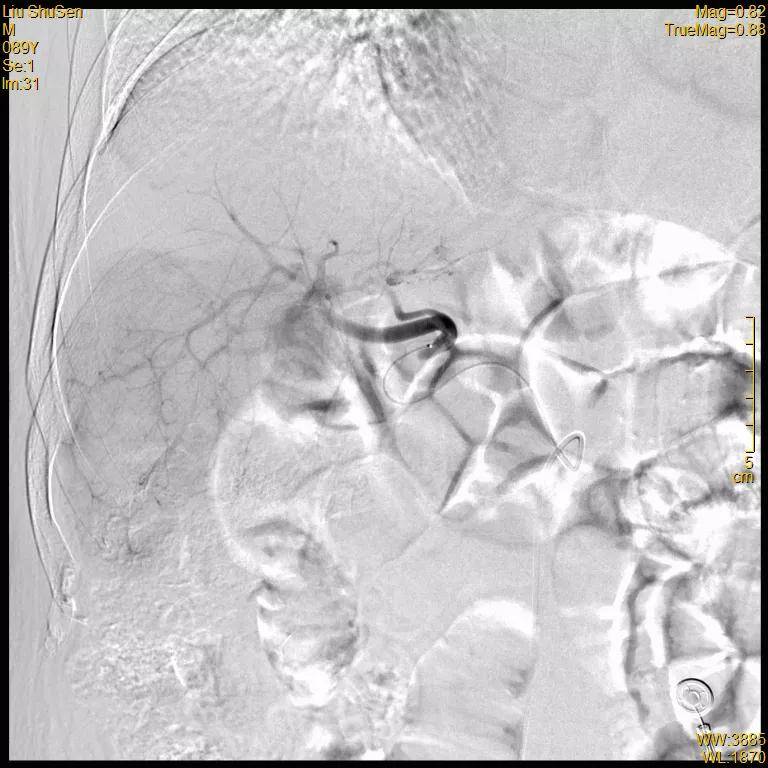

治疗经过:2020-12-18 行TACE术

腹腔干造影

文章图片

肝固有动脉造影

可见肝右叶明确肿瘤染色